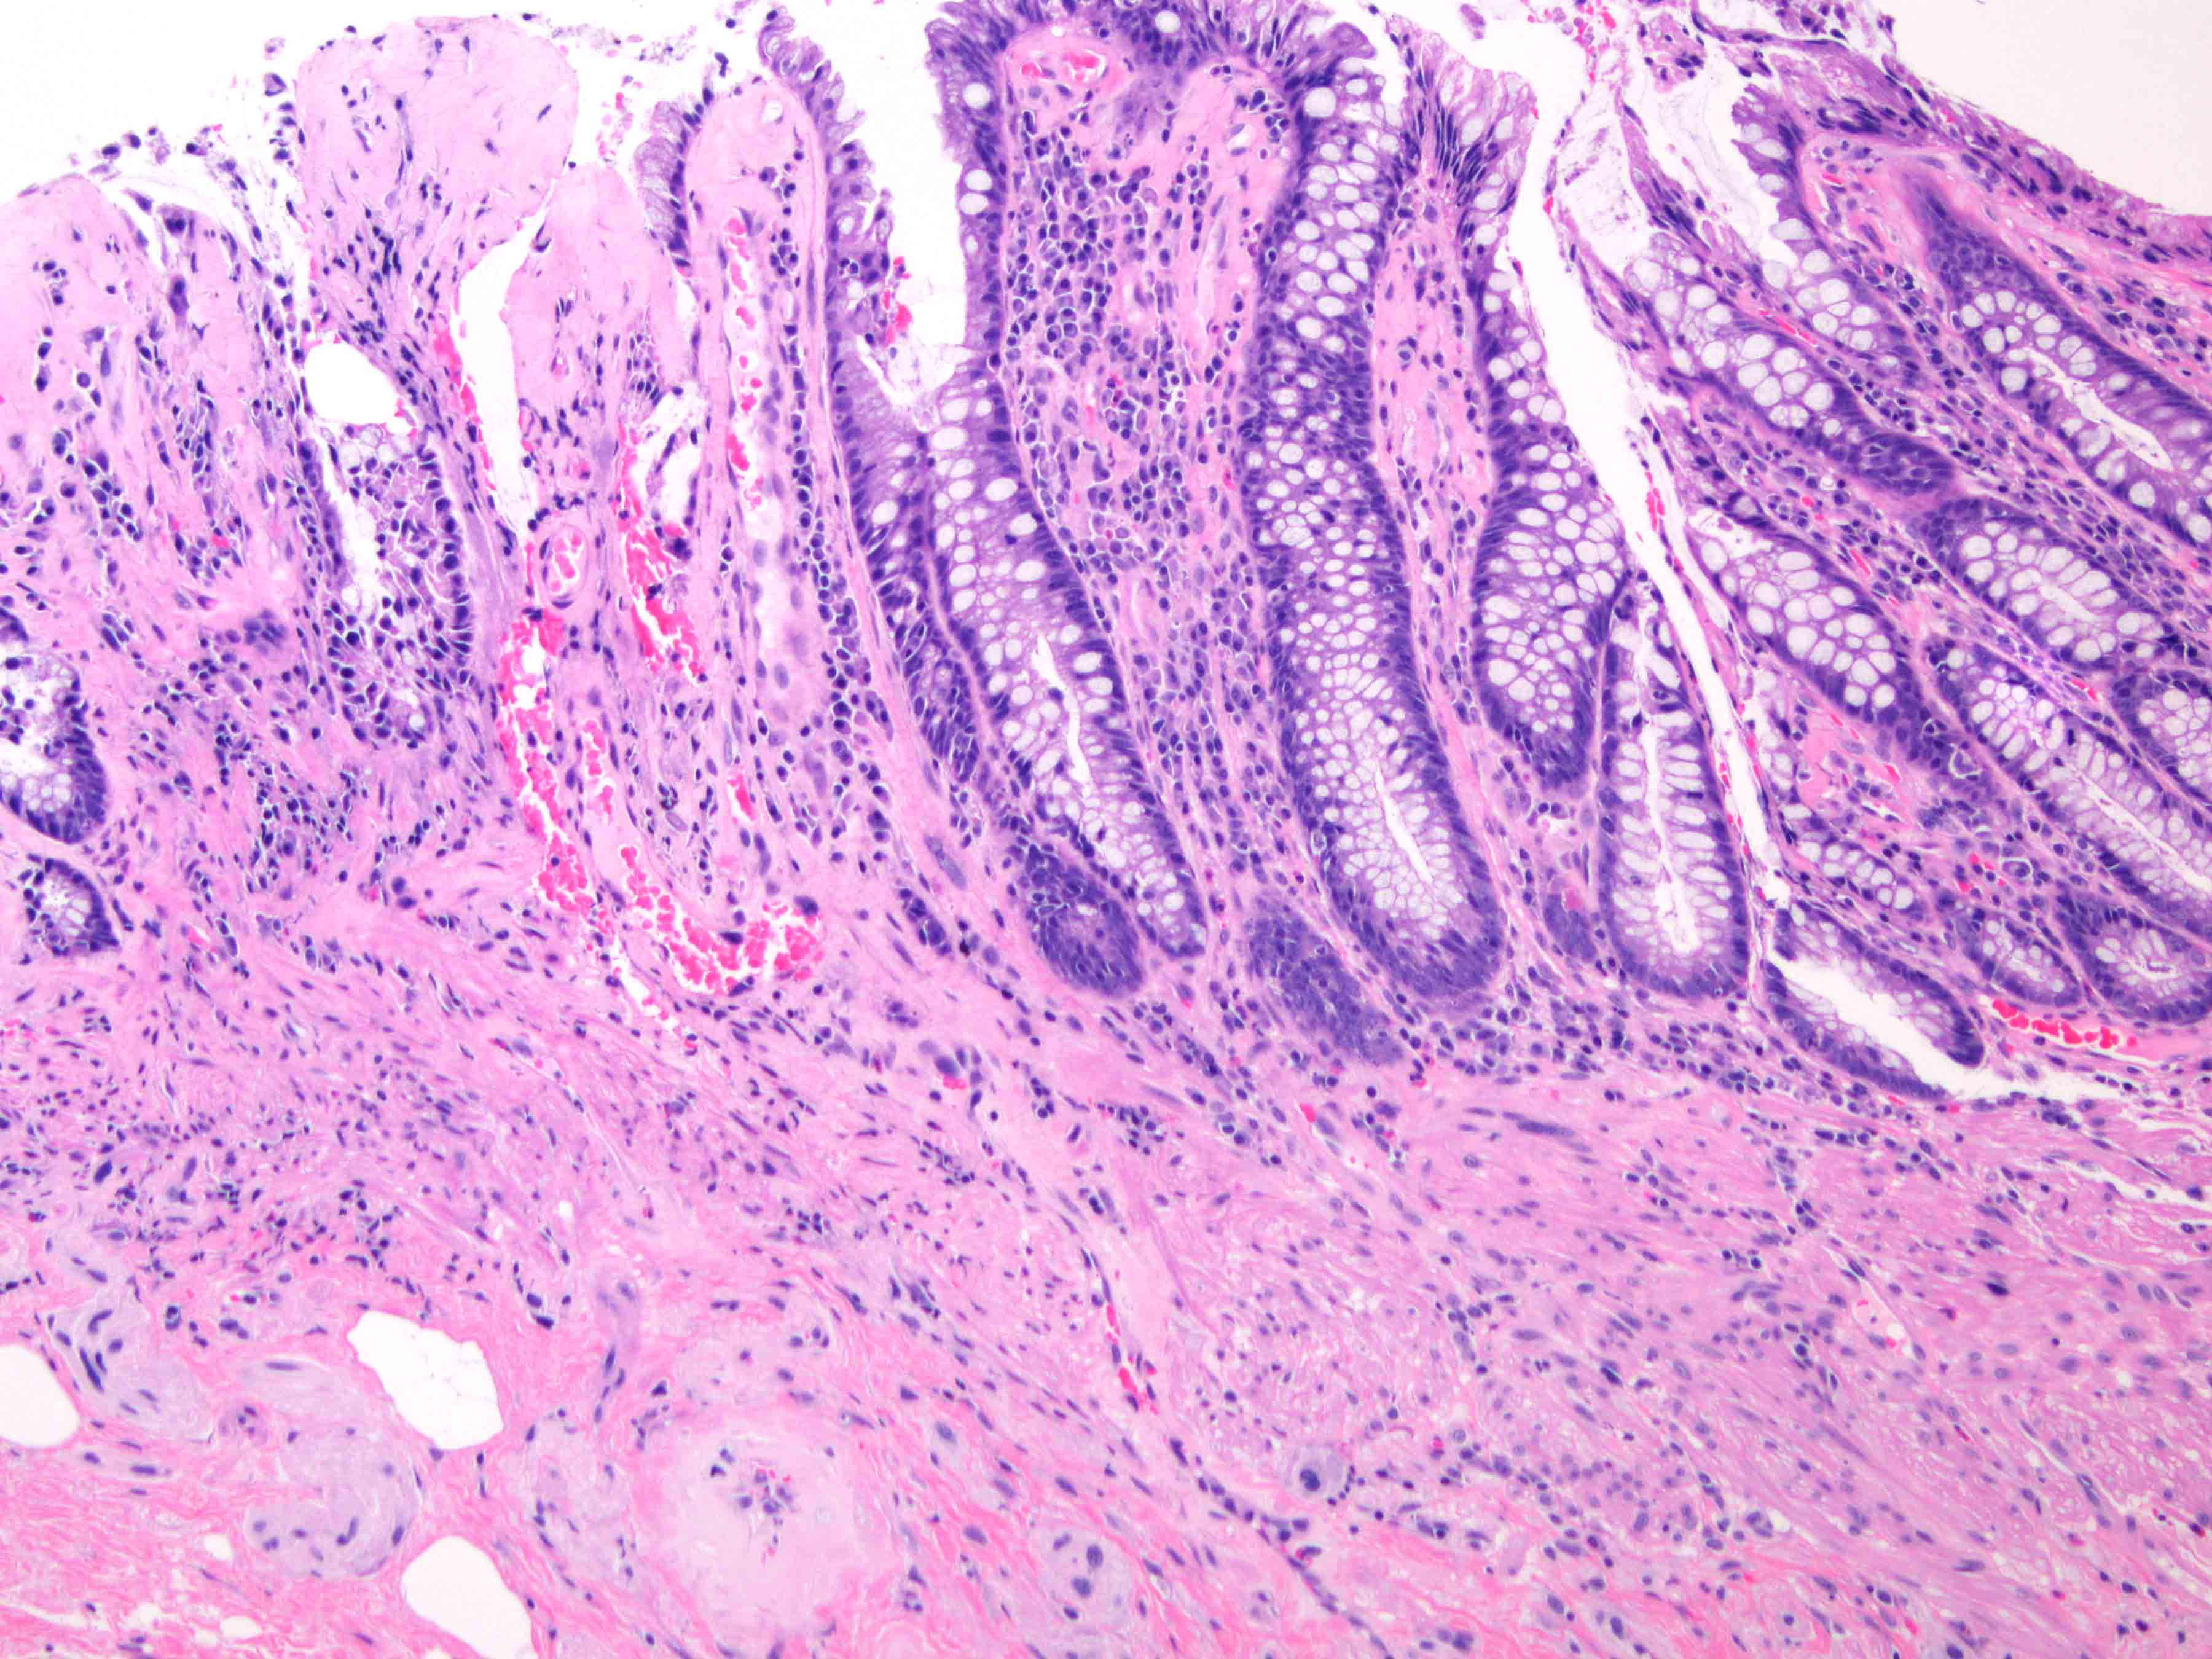

Microscopic (histologic) description

- Chronic radiation colitis (> 6 months after radiation treatment):

- Epithelium:

- Paneth cell metaplasia

- Ulceration

- Mild epithelial atypia

- Crypts:

- Architectural changes and atrophy

- Lamina propria:

- Fibrosis

- Mild chronic inflammation

- Atypical fibroblasts / stromal cells with enlarged hyperchromatic nuclei

- Submucosa and deeper layers:

- Vasculature

- Hyalinization and fibrosis of vessel wall

- Intimal thickening

- Vascular ectasia or narrowing

- Thrombosis

- Endothelial cell atypia

- Vasculature

Microscopic (histologic) images

- Colon, biopsy:

- Colonic mucosa with lamina propria fibrosis and ectatic, hyalinized vessels consistent with mild chronic radiation associated colitis